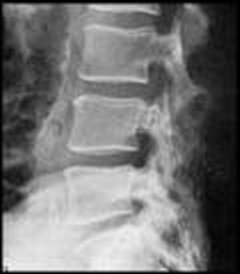

X-Rays

X-rays use electromagnetic waves to create high-quality imaging of the inside of your body. They are a type of radiation best used to photograph hard, dense tissues like bones.